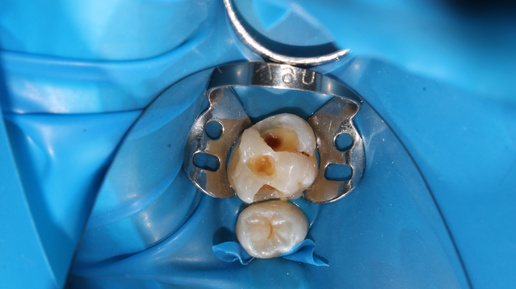

Подготовка зуба к коронке в микроскоп - билдап со стекловолоконным штифтом

Лечение проводят за три-четыре визита. Сначала пролечивают корневые каналы зуба и устанавливают в них штифты. С помощью композитного материала вокруг штифтов формируют искусственную культю зуба, которую затем покрывают коронкой. Когда зуб сильно разрушен, устанавливать искусственную коронку по сути не на что. В таких случаях коронковую часть зуба часто «наращивают» пломбировочным материалом. А чтобы укрепить конструкцию «пломба-зуб», в корневые каналы устанавливают стержни — штифты. Чаще стоматологи...